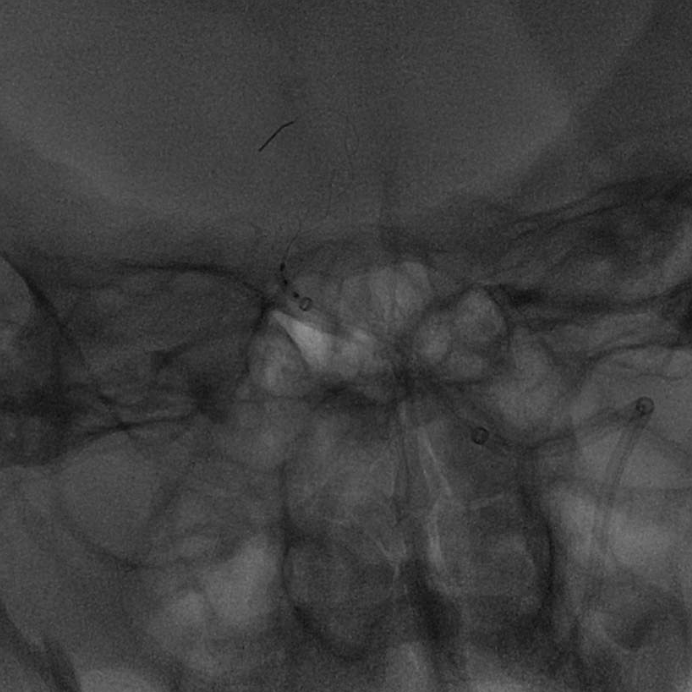

运用BASIS技术植入3.0*25mm Syphonet®取栓支架,输送球囊对闭塞段进行扩张。

运用BASIS技术回收3.0*25mm Syphonet®取栓支架及6F 125cm Tethys®中间导引导管,取出血栓,并在左侧椎动脉V4段残余狭窄处置入颅内支架系统;

复查造影:左侧椎动脉、双侧大脑后动脉、小脑上动脉、小脑前下动脉显影正常。